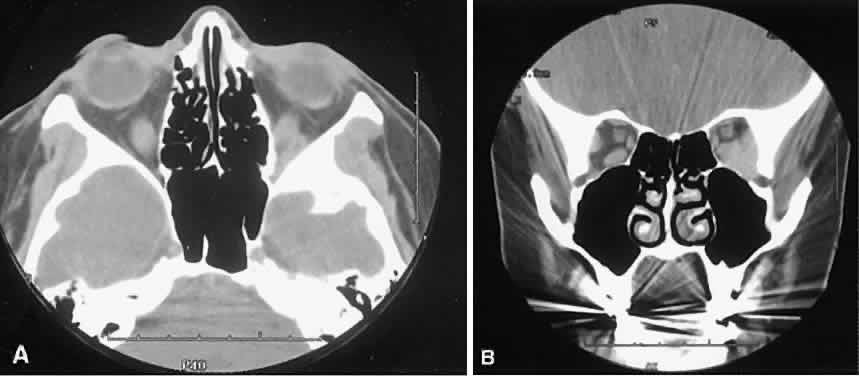

| The orbital manifestations of a vascular process are dependent on whether

the lesion is on the venous or the arterial circulation. Patients with

venous lesions (varix) characteristically report a history of intermittent

proptosis with either a Valsalva's-type maneuver or having

the head in a dependent position. Suspicion of a venous varix should

alert the radiologist to perform the scan before and after a Valsalva's

maneuver.9,10 Color flow doppler imaging showing reversal of flow during a Valsalva

maneuver also is a helpful finding. Phleboliths may or may not be present. Another

clue to the diagnosis of a varix is the location, many times

in the posterior, inferior lateral orbit, seemingly coming out of

the inferior orbital fissure near the apex. Lesions that appear to change

size or shape from the axial view to the coronal view also have turned

out to represent a varix based on our experience (Fig. 2). Arterial lesions may either have high or low flow. The high-flow lesions are carotid cavernous sinus fistulas and result from a direct communication between the carotid artery and the cavernous sinus. These arise spontaneously or as a result of trauma. The orbit is involved as an innocent bystander, because all signs and symptoms of orbital involvement follow from the retrograde transmission of increased venous pressure from the cavernous sinus. EOMs generally are enlarged, as is the SOV. The ipsilateral cavernous sinus also is enlarged. Intercommunication between the cavernous sinuses also may account for the occasional bilateral findings. Low-flow lesions result from increased blood flow through the cavernous sinus, but the intracavernous carotid artery itself is intact (Fig. 3). These typically are dural-cavernous sinus fistulas. A high index of suspicion may be required to diagnose these, but a fairly stereotyped presentation is a unilateral red-eyed glaucoma with proptosis. Abduction weakness also may be present. Enlargement of one or more EOMs along with an enlarged SOV are noted with CT scanning. A small lesion may escape detection with CT scanning and require high-resolution MRI or even selective internal and external carotid angiography for diagnosis if a high degree of clinical suspicion exists. In a patient with a known dural fistula, a sudden and dramatic deterioration in the clinical picture may be seen with a thrombosis of the SOV.11 The radiographic picture, at least regarding the CT appearance, probably will not change. MRI can nicely show the thrombosis in the SOV.